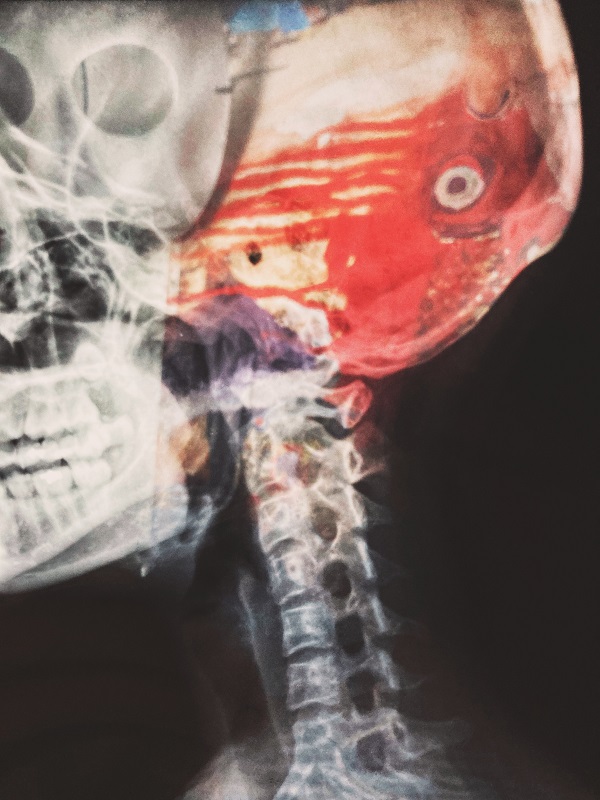

O AVC (Acidente Vascular Cerebral) acontece quando os vasos responsáveis por levar o sangue até o cérebro entopem ou se rompem, causando assim morte dos neurônios da área cerebral que ficou sem a circulação sanguínea. Por esse motivo, quanto antes identificado e iniciado o tratamento, menores são as chances de danos mais graves ao paciente.

Outros sintomas ainda podem ser: dificuldade de caminhar ou ficar em pé; formigamento e falta de força em um lado do corpo; problema de memória recente e passada; e dor de cabeça intensa com vertigem. O tratamento precoce com medicamentos, como TPA (anticoagulante), pode minimizar danos cerebrais por isso é importante buscar auxílio médico imediatamente.